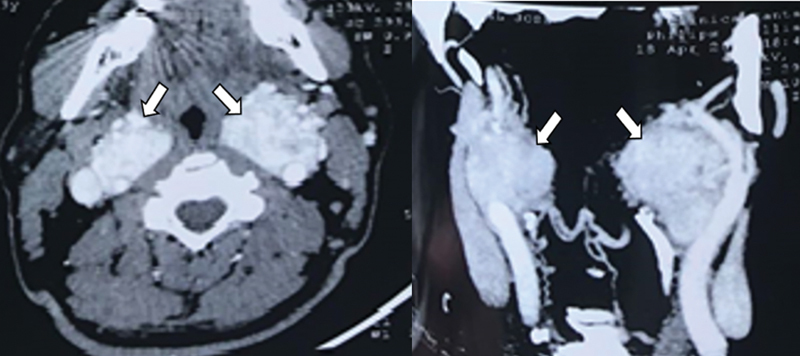

Obstructive sleep apnea (OSA) is often associated with reduced pharyngeal muscle tone and an anatomically narrowed pharyngeal airspace. We try to describe two cases with OSA that were diagnosed with vascular lesions during DISE: One of them was an aberrant internal carotid artery, and the second one was a glomus tumor. These anatomic anomalies contribute to airspace narrowing in these patients. These two cases describe an exciting presentation of sleep apnea and remind us of the importance of clinically recognizing vascular alterations to avoid damage during routine oropharyngeal procedures.